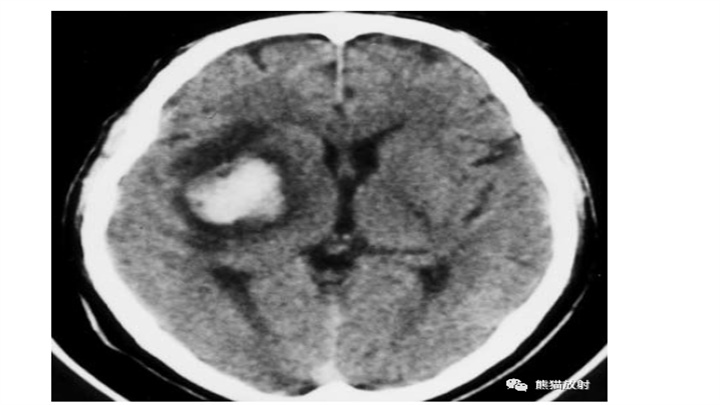

丘脑血肿,范围有限,保守治疗即可。对侧顶叶低密度楔形病变,陈旧性脑梗死。血肿占位效应明显(第三脑室变形)和脑室内积血,具有致命的后果。